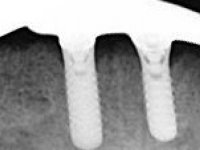

Then, the teeth were mounted in the screwed record bases and function and aesthetics were clinically evaluated. After these evaluations, the dental technician develops silicone walls that guide the fabrication of the milled bars. The precise passive fit of the bars was checked clinically and with radiographs. Then, a pick-up impression with an individualized tray was done to achieve a functional impression of the soft-tissues.